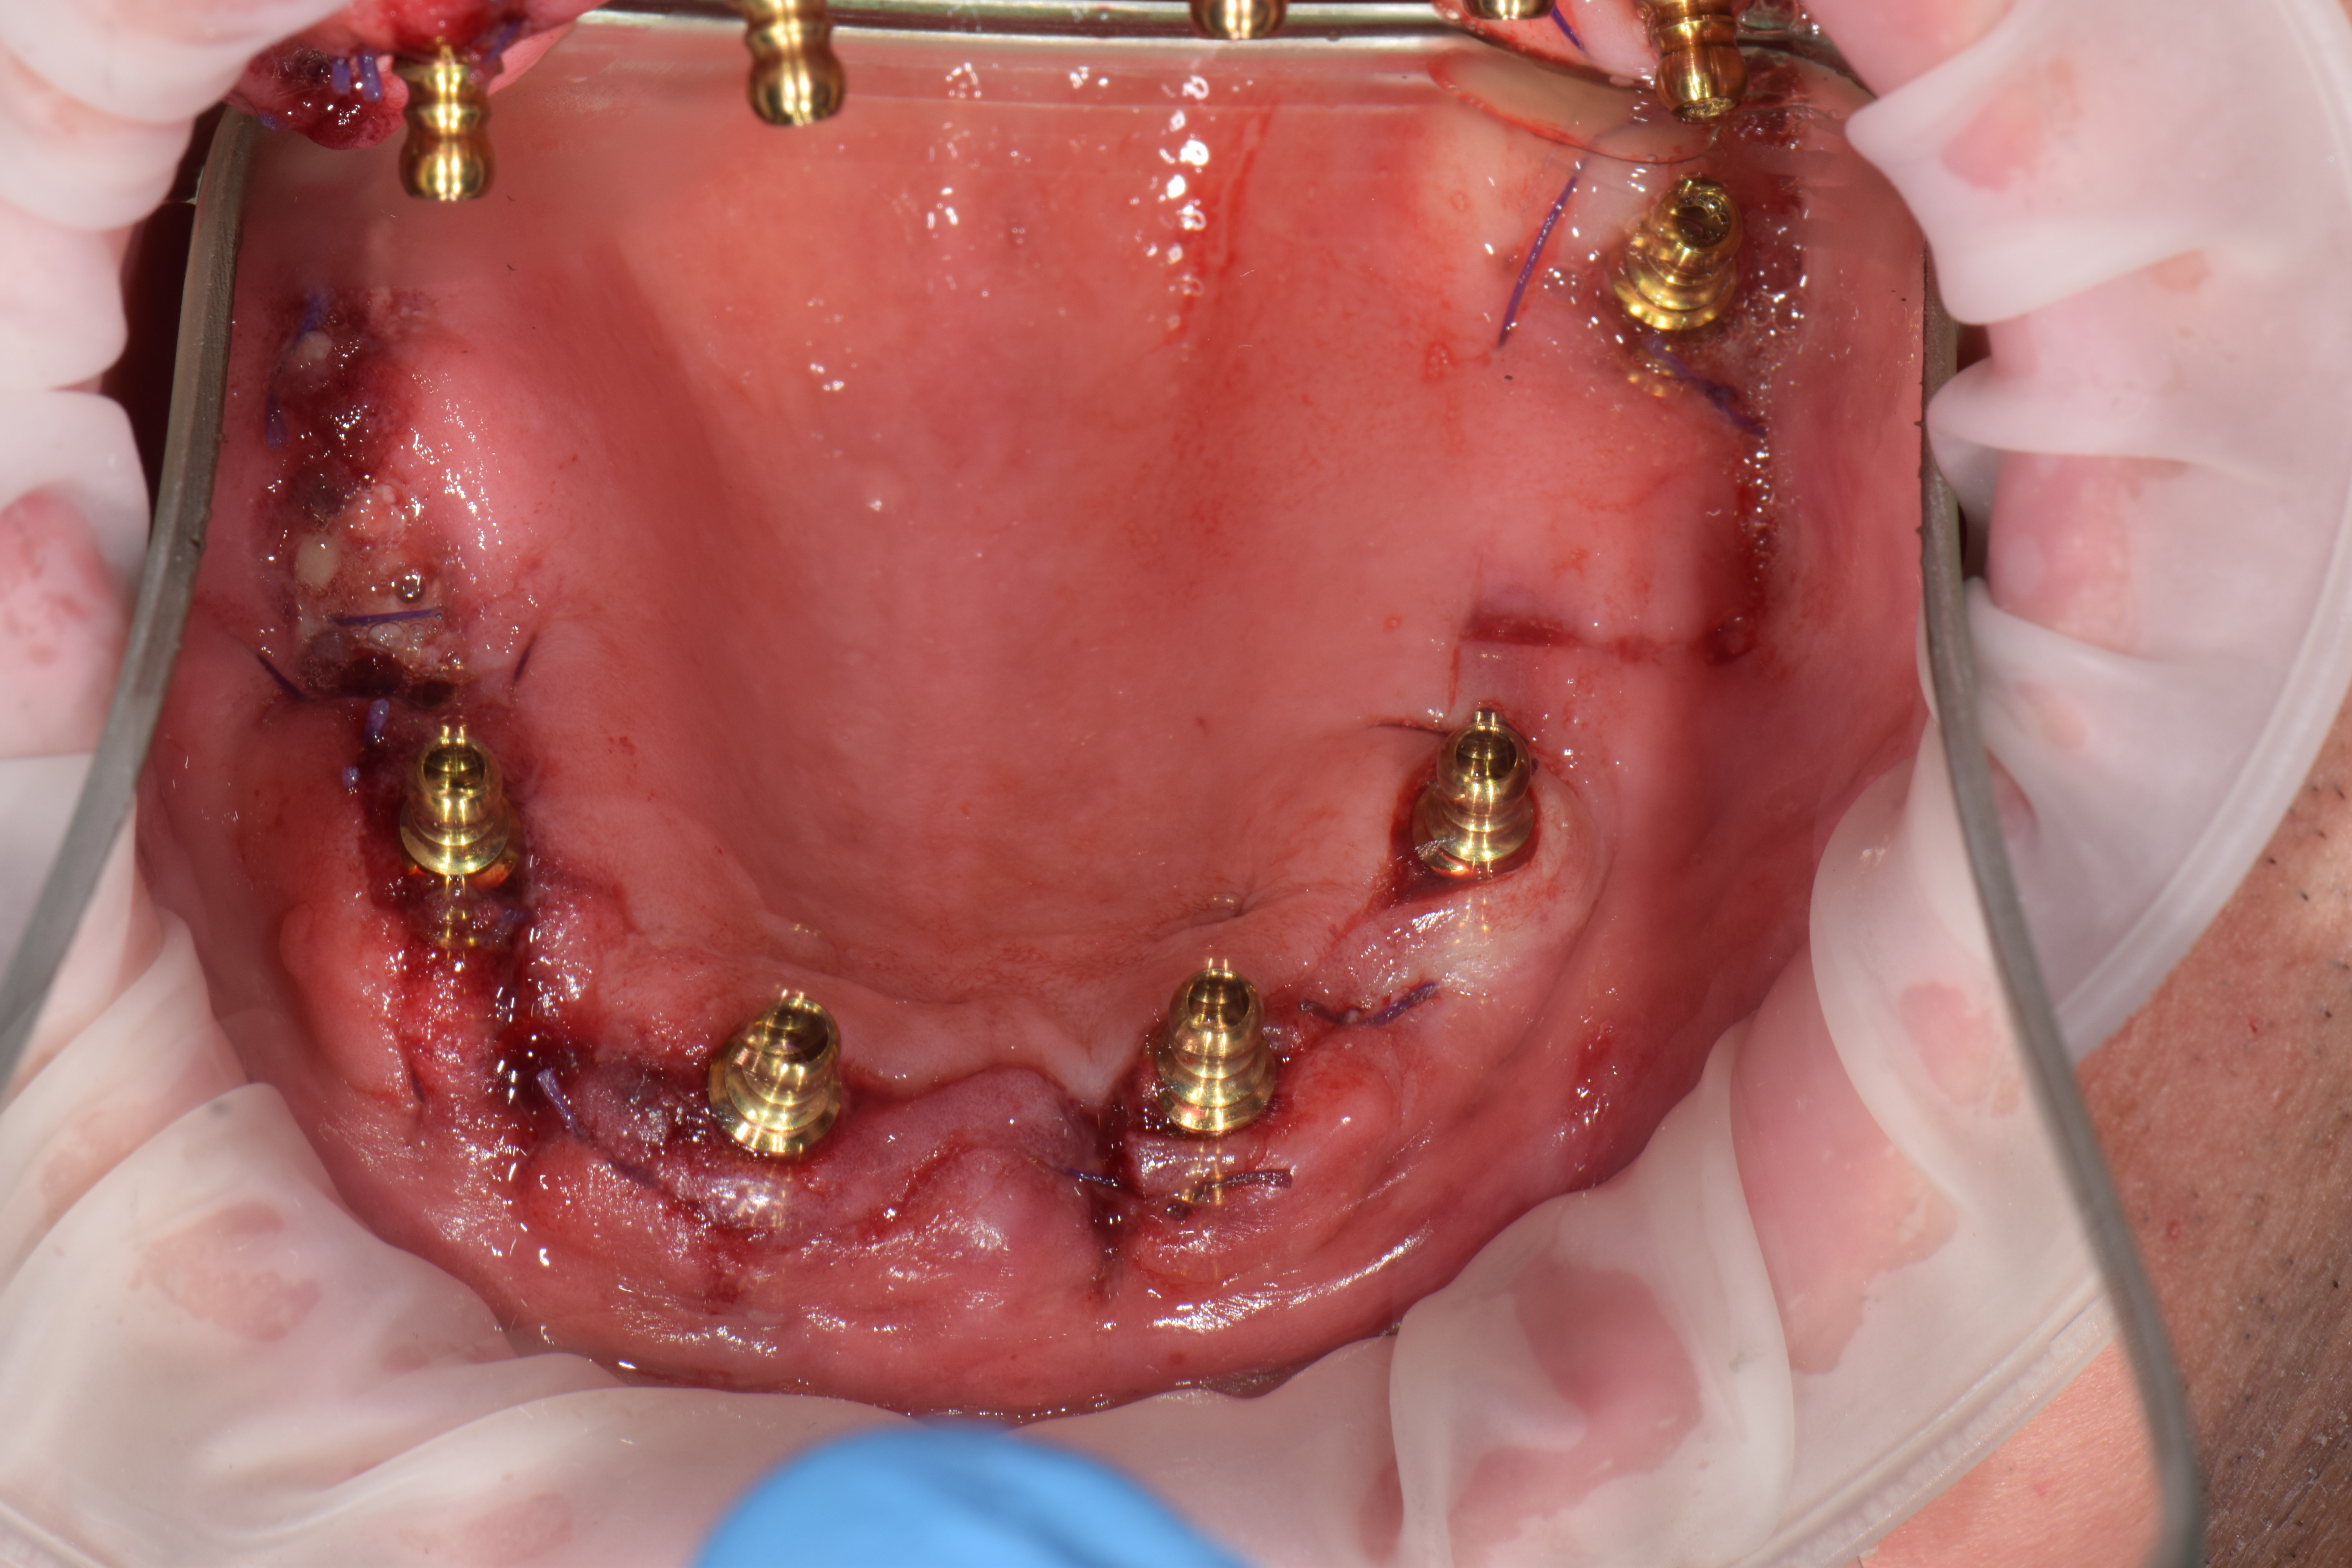

| ИМПЛАНТАЦИЯ |

|

|

|

|

|

|